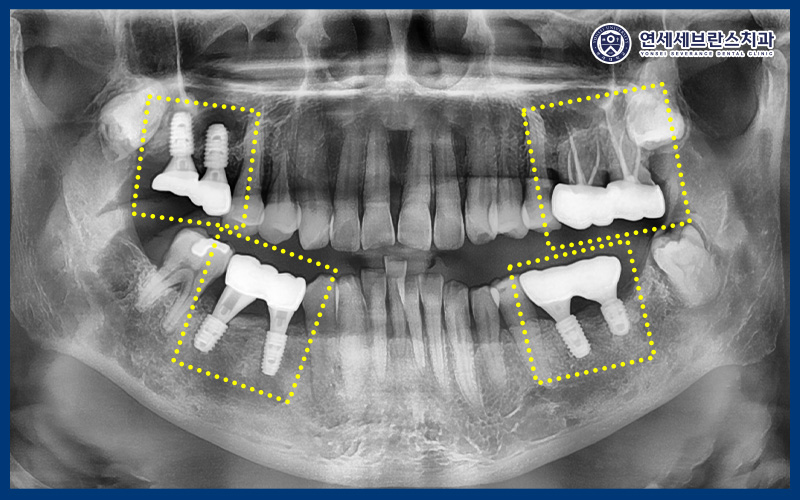

26.02.06

파노라마 상에서도

임플란트 주변과 기존 치료 부위 모두

염증 소견 없이 깨끗하게 유지되고,

치조골 역시 안정적으로 유지되고 있었습니다.

초기 염증이 심했던 만큼

꾸준한 관리가 중요했던 사례였지만,

안내드린 관리 방법을 잘 실천해 주신 덕분에

재발 없이 양호한 상태를 유지하고 계셨습니다.